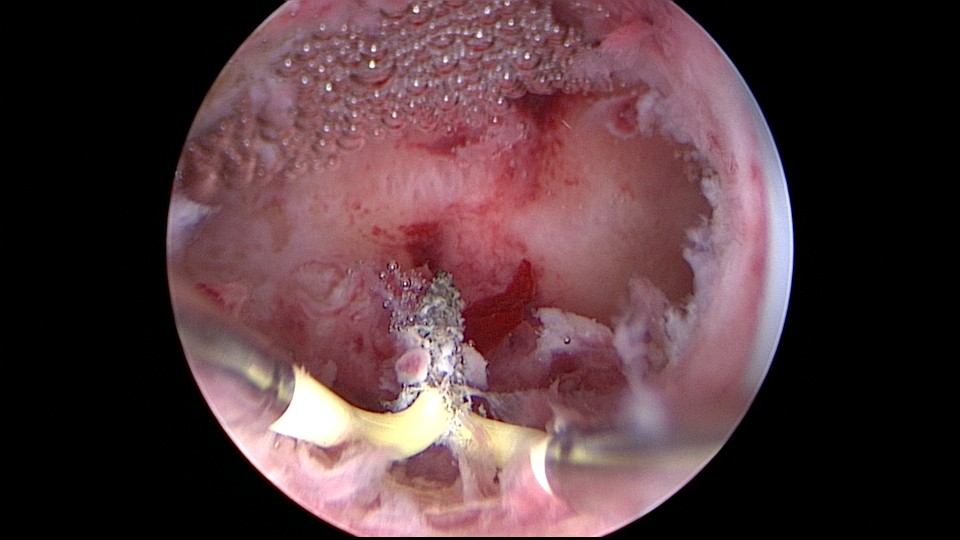

患者35岁,G5P0,继发不孕10年,10年前外院开腹宫外孕手术1次,试管失败1次。外院B超提示宫腔粘连,2021年4月在成都西囡妇科医院做宫腔镜检查,发现宫腔粘连。2021年11月到我院做宫腔镜分粘手术,术中见宫腔两侧及右侧宫角致密粘连,内膜片状充血,单极电切分粘,恢复宫腔形态,显露双侧输卵管开口。2021年12月宫腔镜二探取球囊,宫腔形态正常,双侧输卵管开口可见。分粘后再次试管成功,足月分娩。现40岁,G6P1。